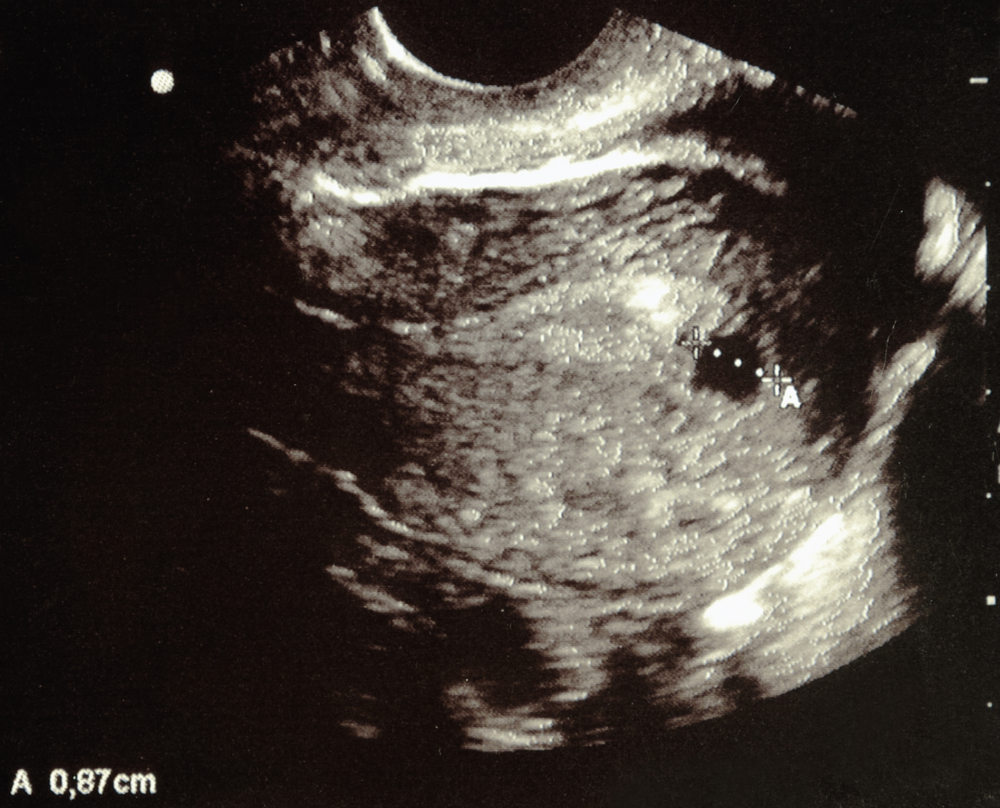

No, at 6 weeks, the baby is just about the size of a pea and is even difficult to find on an ultrasound scan. If you take a scan this early, it will be a transvaginal scan to check the site of implantation. The limb buds just begin to appear, so for the baby to make any movements, you will have to wait a few more weeks.

At 6 weeks of pregnancy, an early ultrasound known as a viability scan may be performed. The scan intends to check if the pregnancy is developing correctly and if the embryo has implanted inside the uterus. Your doctor may suggest such an early scan if you experience any pain or bleeding.

At 6 weeks, a transvaginal ultrasound can visualize the gestational sac and yolk sac. In the case of twins, they can see two sacs. However, they can miss a twin if one sac is hidden behind the other or if the twins share a sac. Twins sharing a sac are very rare and are called monoamniotic-monochorionic (MCMA) twins.